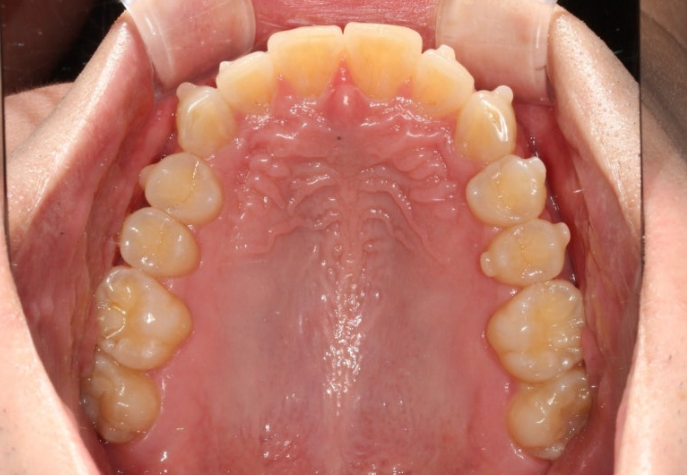

25년 2월부터 6월까지 14개 첫세트 장치를 모두 낀 후 모습입니다.

과개교합은 대부분 개선되었고 중심선 불일치도 개선되었습니다.

일부 배열상 미진한 부분을 추가로 개선하기 위해 추가장치 제작에 들어갔고 25년 12월 드디어 치료를 마무리 했습니다.